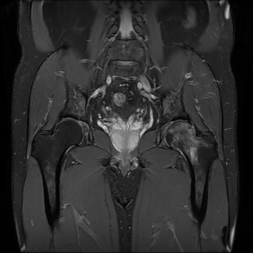

近日,一位50岁男性患者,因左髋部疼痛伴活动受限4月到我院疼痛科就诊,完善双侧髋关节MRI平扫提示:双侧股骨头及左侧股骨颈异常改变,考虑:股骨头缺血坏死(左侧约为Ⅲ期,右侧为I期),经院内多学科联合会诊,并邀请建站专家解放军联勤保障部队第九二〇医院骨科徐永清教授专家团队进行远程会诊参与病例讨论。

术前MRI